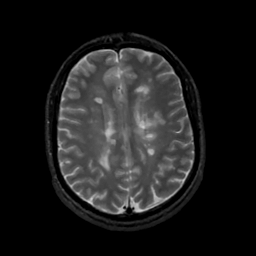

MR Study #10, April 28, 1991 -- Slice #33

[Home][Help][Clinical][Tour 1][Tour 2] Slice 33